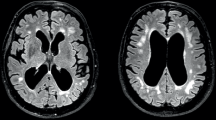

Bi-transgenic mouse model of DM1

To test the TR construct as a splicing biomarker for DM1, we crossed TR transgenic mice with HSALR transgenic mice (both on the FVB background) to produce homozygous TR+/+;HSALR+/+ bi-transgenic mice (Supplementary Fig. 3; Supplementary Table 1). Quantitative in vivo fluorescence imaging of gastrocnemius and lumbar paraspinal muscles of TR;HSALR bi-transgenic mice revealed a low DsRed/GFP ratio, as compared to TR single transgenic mice (Fig. 2a, b). RT-PCR analysis of muscle tissue confirmed the splice switch in TR;HSALR mice, while higher GFP expression also was evident in bi-transgenic mice by Western blot (Fig. 2c–e). Quantitative fluorescence microscopy of muscle cryosections demonstrated bright DsRed and low GFP expression in TR single transgenic, and low DsRed and high GFP expression in TR;HSALR bi-transgenic mice (Fig. 2f). Muscle histology in TR transgenic mice was similar to wild-type, and TR;HSALR bi-transgenic mice appeared similar to HSALR single transgenic mice (Fig. 2f).

TR;HSALR bi-transgenic mice as a therapy reporter model for DM1. In the HSALR transgenic mouse model of DM1, exclusion of Atp2a1 exon 22 is upregulated. To validate the TR-ATP2A1 splice switch as a reporter for DM1, we crossed the TR transgenic with the HSALR transgenic model to create TR;HSALR bi-transgenic mice. a In vivo imaging of DsRed and GFP fluorescence in TR transgenic and TR;HSALR bi-transgenic mice (IVIS Spectrum) under general anesthesia in the prone position. The scale shows radiant efficiency (photons/second/cm2). Bars = 5 mm. b DsRed and GFP fluorescence measured in regions of interest in bilateral gastrocnemius (Gast) and paraspinal (P-sp) muscles of TR (N = 4) and TR;HSALR mice (N = 3). Error bars indicate mean ± s.e.m. ****P < 0.0001 TR vs. TR;HSALR (one-way ANOVA). c Splicing analysis in gastrocnemius muscle by RT-PCR of the TR transgene (Tg) exon 22 (ex 22) and endogenous Atp2a1 ex 22. N = 3 each group. WT FVB wild-type. d Quantitation of splicing results in c, displayed as the percentage of exon 22 inclusion. Error bars indicate mean ± s.e.m. ****P < 0.0001 (two-way ANOVA). e Western blot of GFP protein expression in gastrocnemius and paraspinal muscles of TR and TR;HSALR mice (N = 3 each group), with GAPDH as loading control. kD kilodaltons. f Representative DsRed and GFP expression in TR (upper row) and TR;HSALR (lower row) gastrocnemius muscle cryosections. Fluorescence images are the extended focus of deconvolved Z-series. Fluorescence intensity range = 0–5080 grayscale units. Laminin (yellow) and DAPI (blue) highlight muscle fibers and nuclei, respectively. Merge DsRed (red) + GFP (green) + laminin + DAPI, H&E hemotoxylin and eosin. Bars = 50 μm